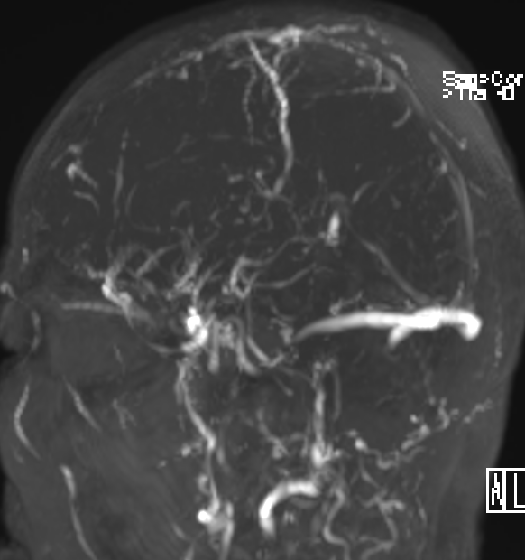

2013-5-16 MRI

2015-1-30 DSA